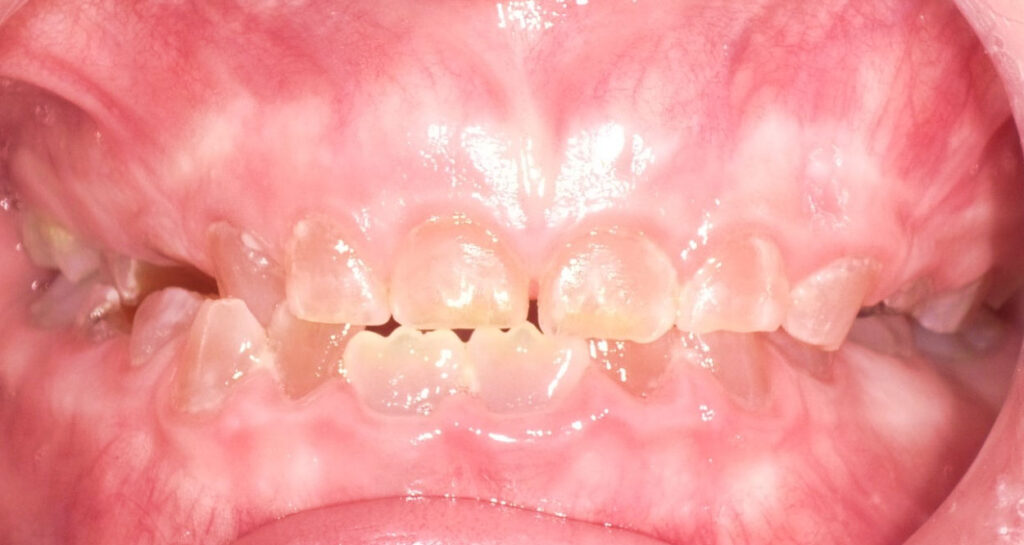

1-month-old girl with mandibular incisor

A 1-month-old girl with a mobile primary mandibular incisor.